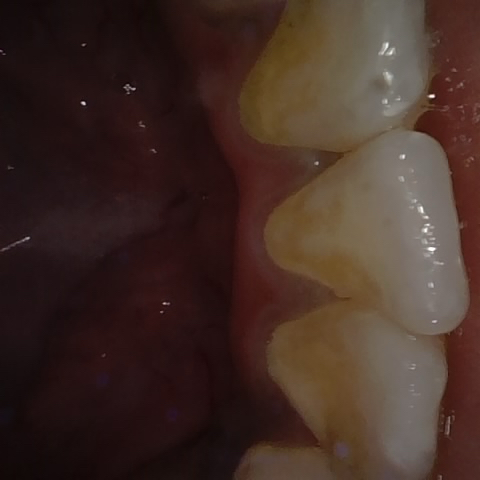

Annotated as "Good"